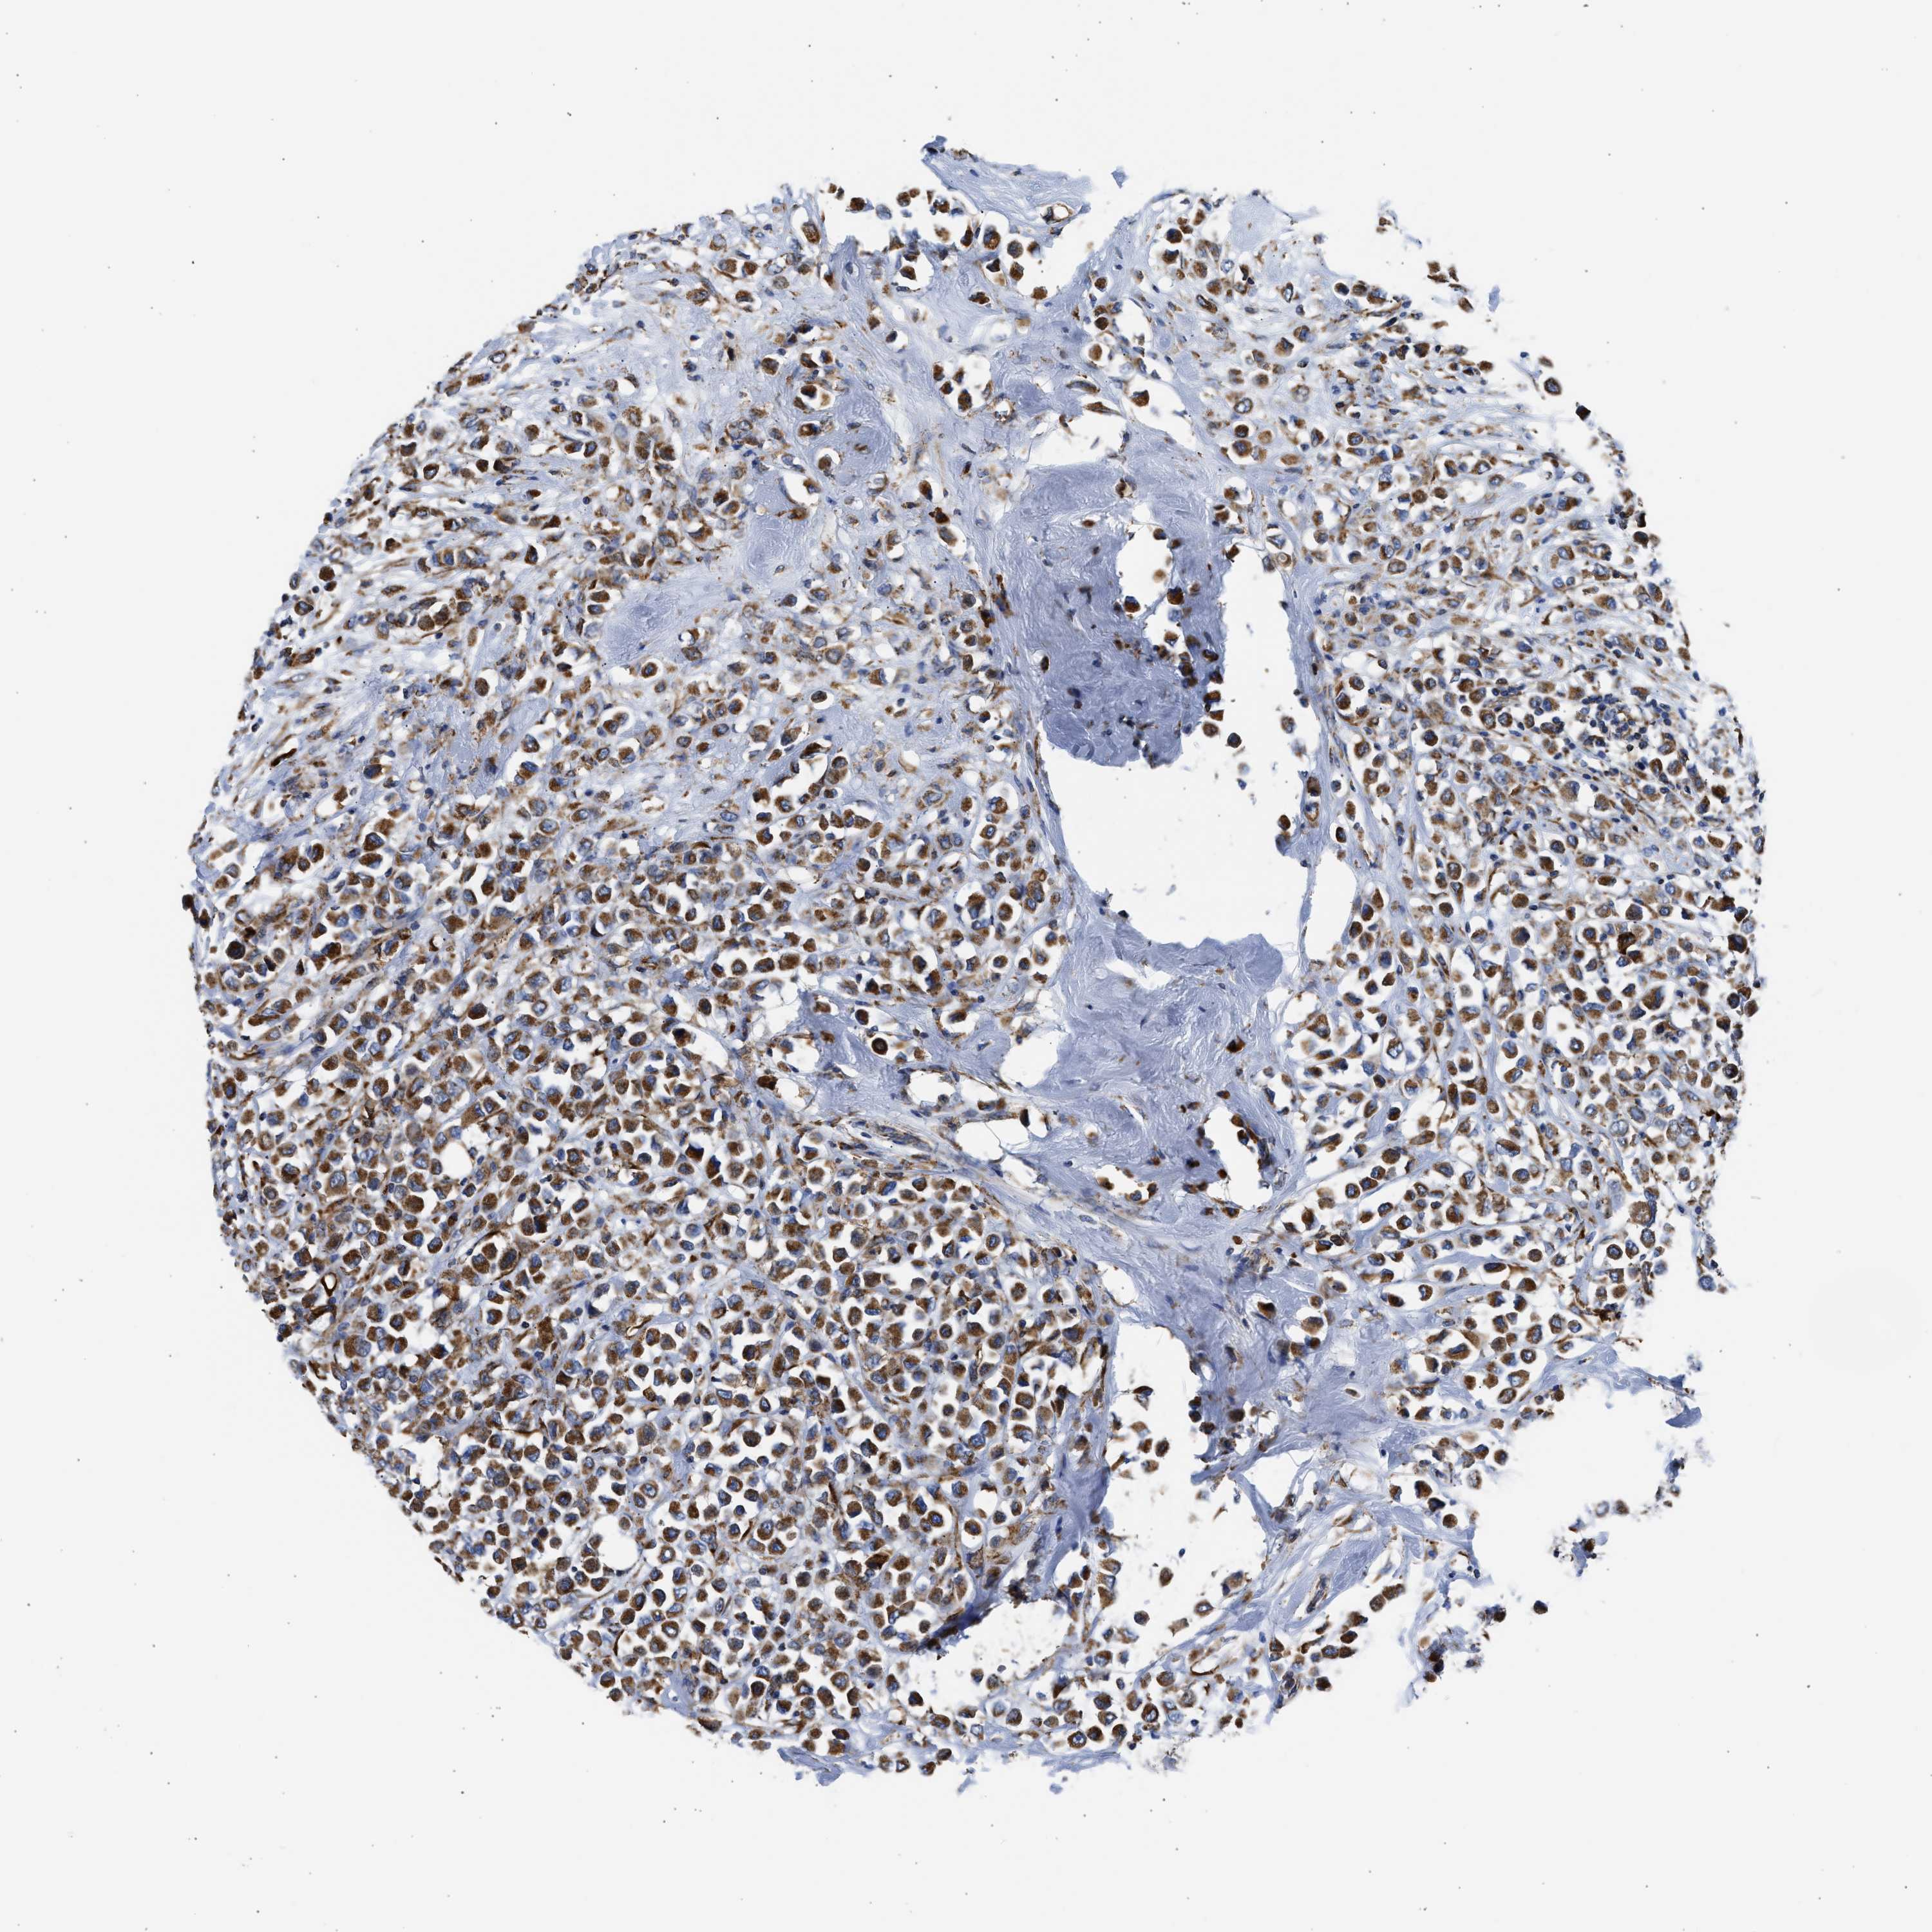

CANCER BREAST CANCER Show tissue menu

BRCA TCGA BRCA VALIDATION PROTEIN EXPRESSION

ANTIBODIES

AND

VALIDATION